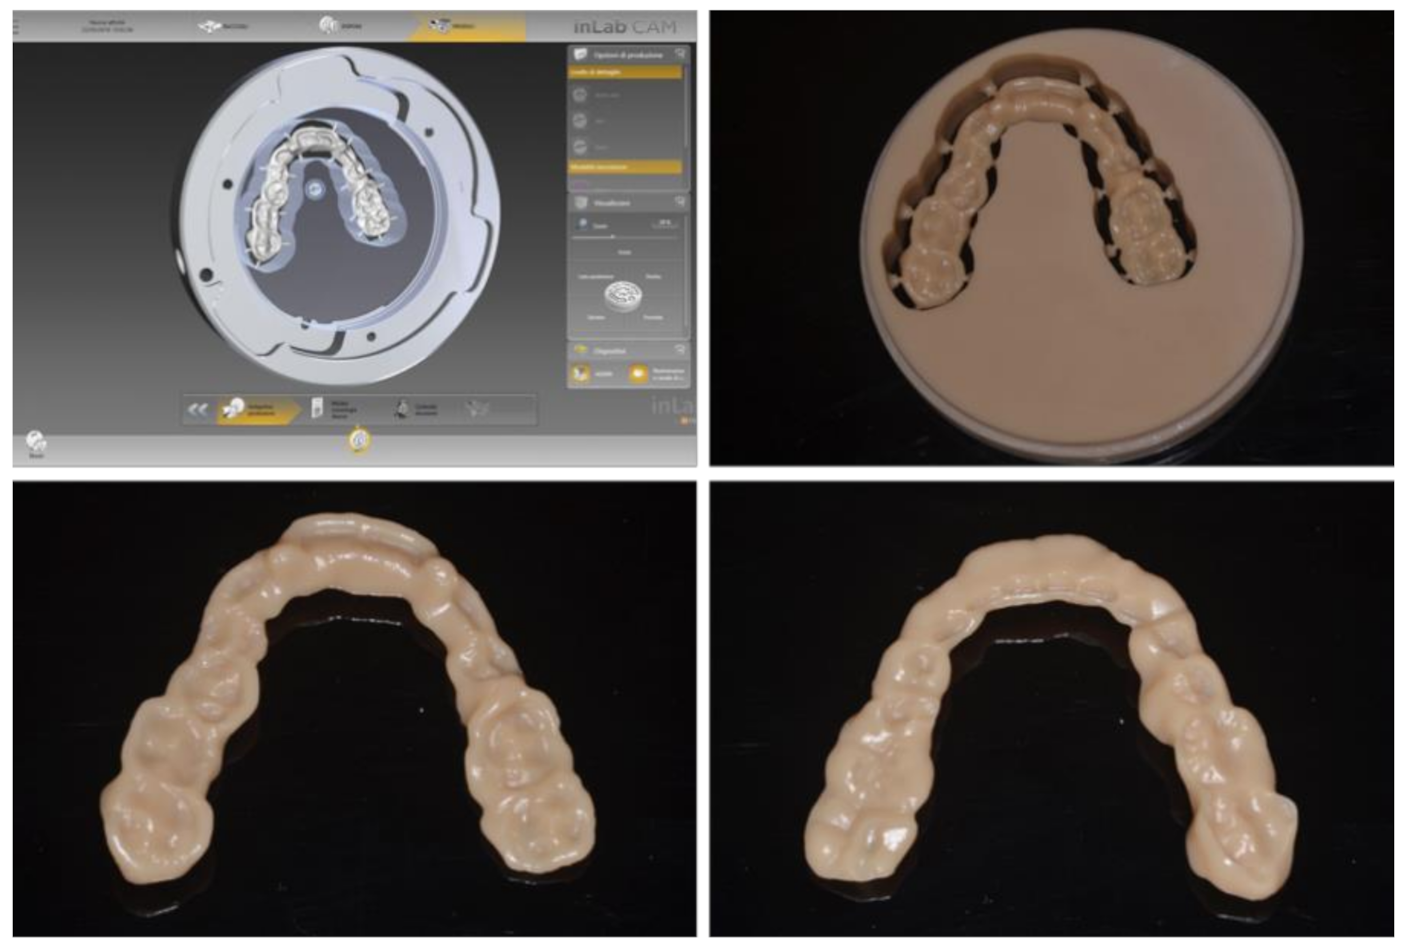

2. Materials and Methods

3. Results